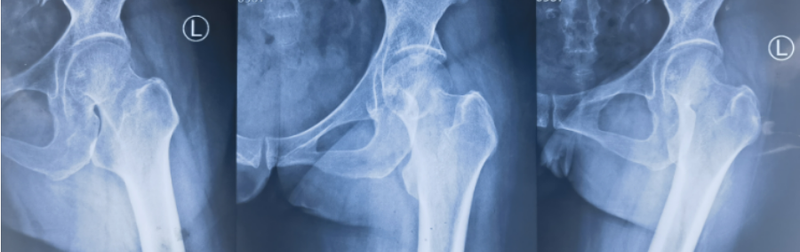

股骨頸骨折是骨科常見病,其并發(fā)癥之一是股骨頭壞死。這一并發(fā)癥的發(fā)生與否,受多種因素的影響,包括患者的年齡、骨折的移位程度、手術(shù)的時(shí)機(jī)與質(zhì)量、術(shù)后負(fù)重的時(shí)間和方式、丟拐的時(shí)機(jī),以及內(nèi)固定物(如釘子)的取出是否合適等。首先,患者的年齡是一個(gè)重要的影響因素。老年人由于骨質(zhì)疏松和血管老化等原因,骨折后股骨頭壞死的發(fā)生率相對(duì)較高。年輕人骨質(zhì)雖好,但往往致傷暴力更大,因此移位大的股骨頸骨折股骨頭壞死的風(fēng)險(xiǎn)亦高。此外,手術(shù)的時(shí)機(jī)和質(zhì)量也是影響股骨頭壞死風(fēng)險(xiǎn)的重要因素。早期進(jìn)行手術(shù)可以有效地減少骨缺血時(shí)間,從而降低股骨頭壞死的風(fēng)險(xiǎn)。同時(shí),手術(shù)的質(zhì)量直接關(guān)系到術(shù)后股骨頭壞死的風(fēng)險(xiǎn)。術(shù)后及時(shí)藥物介入,服用活血化瘀、補(bǔ)肝腎壯筋骨的藥物,能縮短骨愈合的自然時(shí)間,自然也能降低骨折不愈合、骨壞死的風(fēng)險(xiǎn)。在術(shù)后康復(fù)階段,負(fù)重的早晚和丟拐的時(shí)機(jī)也會(huì)影響股骨頭壞死的風(fēng)險(xiǎn)。過早地進(jìn)行負(fù)重可能會(huì)導(dǎo)致骨折端承受過大的壓力,增加內(nèi)固定失效、股骨頭壞死的風(fēng)險(xiǎn)。而丟拐的時(shí)機(jī)也需要根據(jù)患者的恢復(fù)情況來決定。如果丟拐過早,可能會(huì)導(dǎo)致骨折端受力不均,增加股骨頭壞死的風(fēng)險(xiǎn)。?最后,內(nèi)固定物的取出是否合適也會(huì)對(duì)股骨頭壞死的風(fēng)險(xiǎn)產(chǎn)生影響。如果內(nèi)固定物取出過早,股骨頭內(nèi)部骨小梁難以適應(yīng)突如其來的應(yīng)力變化,也增加了股骨頭壞死的風(fēng)險(xiǎn)。比如,這樣一位47歲的股骨頸骨折病人,在骨折術(shù)后的發(fā)現(xiàn)股骨頭內(nèi)骨密度異常,如下圖所示:在去偽影技術(shù)的磁共振上會(huì)看到典型的壞死征,如果磁共振機(jī)器一般,會(huì)看到黑乎乎、白花花的一團(tuán)影子,讓醫(yī)生心里嘀咕、病人直接懵逼。遇到這種情況,鑒于認(rèn)知的原因,病人要么疏忽不當(dāng)一回事;要么驚慌失措,趕緊柱上拐杖老老實(shí)實(shí)地窩在家“養(yǎng)”病——越養(yǎng)越重;要么,趕緊上網(wǎng)查秘方,一個(gè)月幾千塊的所謂“祖?zhèn)鳌备嗨帯⒖诜幩藕蛏稀蛟S會(huì)有一丁點(diǎn)兒用。當(dāng)然,這種情況也可以冷靜下來作壁上觀,再觀察觀察看。但問題來了,觀察幾個(gè)月下來,骨吸收更重了怎么辦?不開刀、簡單吃點(diǎn)正兒八經(jīng)的藥,還能干什么?別忘了,還有“不流血的手術(shù)刀”,沖擊波試試呀!來,看我們精準(zhǔn)制導(dǎo)下的沖擊波能量治療:哪地方修復(fù)地慢,哪地方就給它刺激刺激;當(dāng)然只刺激還不行,再配合我院傳統(tǒng)中成藥系列補(bǔ)補(bǔ)營養(yǎng)——對(duì),就這么簡單!打了幾次沖擊波,3個(gè)月后復(fù)查:什么,釘子什么時(shí)候?。窟€問這個(gè)問題?這說明上面的鏈接您沒看吶!再來對(duì)比一下治療前后的骨密度變化:股骨頸骨折并發(fā)股骨頭壞死的因素很多、可能性很大,在骨折治療和康復(fù)過程中,醫(yī)生要根據(jù)患者的具體情況制定個(gè)性化的治療方案和康復(fù)計(jì)劃;同時(shí),患者一定要定期復(fù)查,和醫(yī)生保持密切的溝通和合作,及時(shí)發(fā)現(xiàn)壞死的端倪,第一時(shí)間采取積極措施,以降低股骨頭壞死的風(fēng)險(xiǎn)。